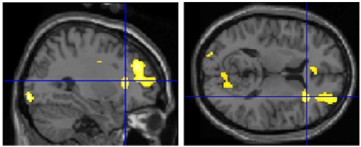

- method: observers naïve to art criticism placed in fMRI while viewing images of Classical and Renaissance sculptures

1) compared brain responses to canonical and modified sculptures

2) compared brain responses to beautiful and ugly sculptures (based on observer’s aesthetic judgment)

- findings: canonical images were strongly preferred over modified images

1) canonical sculptures activated right insula (mediates emotions; connects to/from amygdala): evidence for _________ beauty (“I can see why people like that.”)

right insula activity

2) beautiful images activated right amygdala (responds to learned emotional information): evidence for __________ beauty (“I like that.”)

right amygdala activity

- conclusion: both of these non-mutually exclusive processes contribute to appreciation of artwork